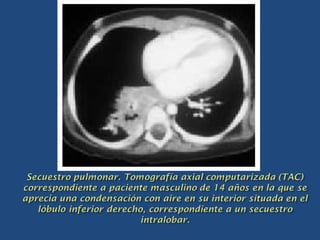

 Se defina como una porción de parénquima pulmonar

aorta.

 El tejido pulmonar secuestrado no es normal, sino que

comunican con el árbol bronquial, se llenan de aire o pus.

 Por su localización, se distinguen dos variedades:

1. Secuestro intralobar.

 El tejido anómalo se encuentra por dentro de la

pleura visceral contiguo al tejido pulmonar

normal.

 En la gran mayoría de los casos se localiza en la

región basal posterior.

 Cuando se establece comunicación con el árbol

bronquial, puede aparecer sintomatología de

broncorrea, hemoptisis e infecciones

recidivantes.

 El diagnóstico exige la aortografía para

visualizar la arteria anómala.